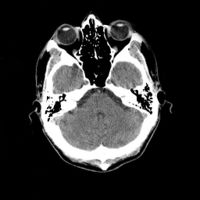

معرض الصور

يوضح ماسح التصوير المقطعي الحاسوبي بدون غلافه كيف يعمل؛ داخل الجهاز الذي يكشف عن داخلك |